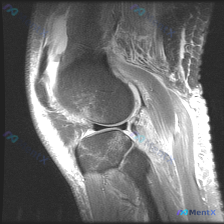

最近碰到一个有意思的读片病例:用户提供了一张膝关节MRI矢状位T1加权图像,主诉提示存在半月板异常,咱们一起来看看这个病例,整理一下思路。 病例核心信息 本次仅提供单张膝关节矢状位T1加权MRI,阅片可见: 1. 骨骼结构:股骨远端、胫骨近端骨皮质连续,骨髓信号符合正常脂肪信号分布,无局灶性异常低信...

刚看到这个膝关节MRI读片的病例,整理一下完整的病例信息和分析思路,和大家讨论一下这种情况的处理。 病例基础信息 本次提供的是单幅膝关节矢状位T1加权MRI影像,核心疑问是评估是否存在半月板异常。 影像学观察结果 我们先按解剖结构整理观察结果: 1. 骨骼结构:股骨远端、胫骨近端、髌骨骨皮质连续,骨...

看到一个很有代表性的读片病例,怀疑半月板异常但单张T1加权MRI没有发现明确问题,整理了分析思路和大家分享。 病例核心信息 问题:临床怀疑半月板异常,提供单张膝关节矢状位T1加权MRI,需要做影像观察和分析 影像系统性观察结果 1. 骨性结构:股骨远端、胫骨近端、髌骨轮廓规整,骨髓信号正常,未见骨质...

今天看到一份很有代表性的读片病例,整理出来和大家分享一下,核心问题就是:临床怀疑半月板异常,但是只给了一张膝关节矢状位T1加权MRI,阅片没发现明确异常,这个情况该怎么分析? 先整理一下这份影像资料的基本信息 这是单张膝关节正中矢状位T1加权像,图像质量清晰,没有运动伪影,能看到股骨远端、胫骨近端、...